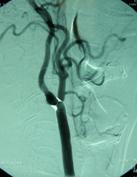

Before surgery, tests such as carotid color Doppler ultrasound, magnetic resonance angiography, or conventional angiography are required. It is important that the patient’s blood pressure is well controlled before surgery.